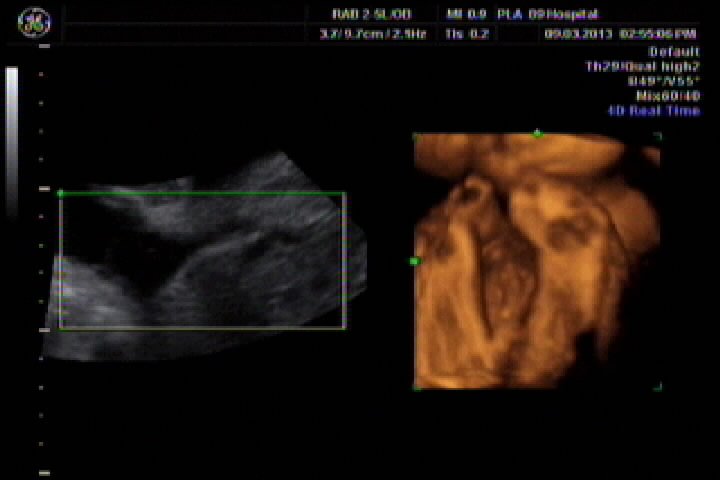

今天刚做了四维彩超,刻了光盘,但不会看,想请专业认识帮我看看胎儿性别,胎儿27周又5天 点击展开 匿名用户 2013-03-10 00:01 为您推荐: 其他回答 你这个大夫估计就是骗你钱呢,打的什么图像,宝宝一点没照到,而且图像特别虚,上面的图片只是羊水和脐动脉,一点实质性内容都没有 宫和玉_XzIQ 2013-03-10 10:16 汗。。。 说了违法。 而且网上的人说了你就信啊。 忽悠你不要钱的。 孟觅翠_RspR 2013-03-10 00:19 相关问题 孕晚期如何测胎儿性别怎样从四维彩超数据看胎儿性别? 多久怀孕可以判断胎儿性别,怎么判断我现在孕7周 14周B超数据如何来判断胎儿性别 前壁,双顶径27,股骨长13,能看出男孩女孩吗?